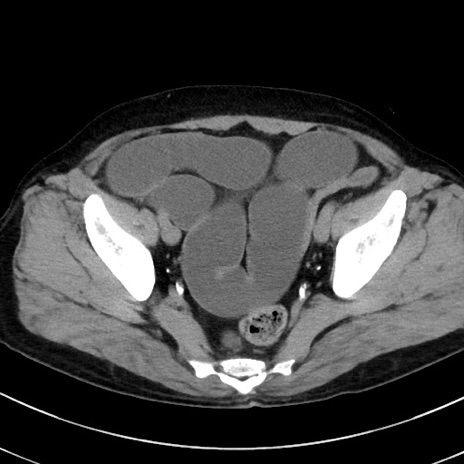

症例38(横断像)

【症例】70歳代 男性

【主訴】腹痛・嘔吐

【現病歴】昨晩より、嘔吐・腹痛あり。今朝になっても嘔吐あり。来院。

【既往歴】心臓バイパス手術、開腹胆摘、腸閉塞

【身体所見】BP 107/71mmHg、HR 116/min、腹部:平坦、軟、下腹部に軽度圧痛あり。反跳痛なし。

【データ】WBC 15100、CRP 0.32